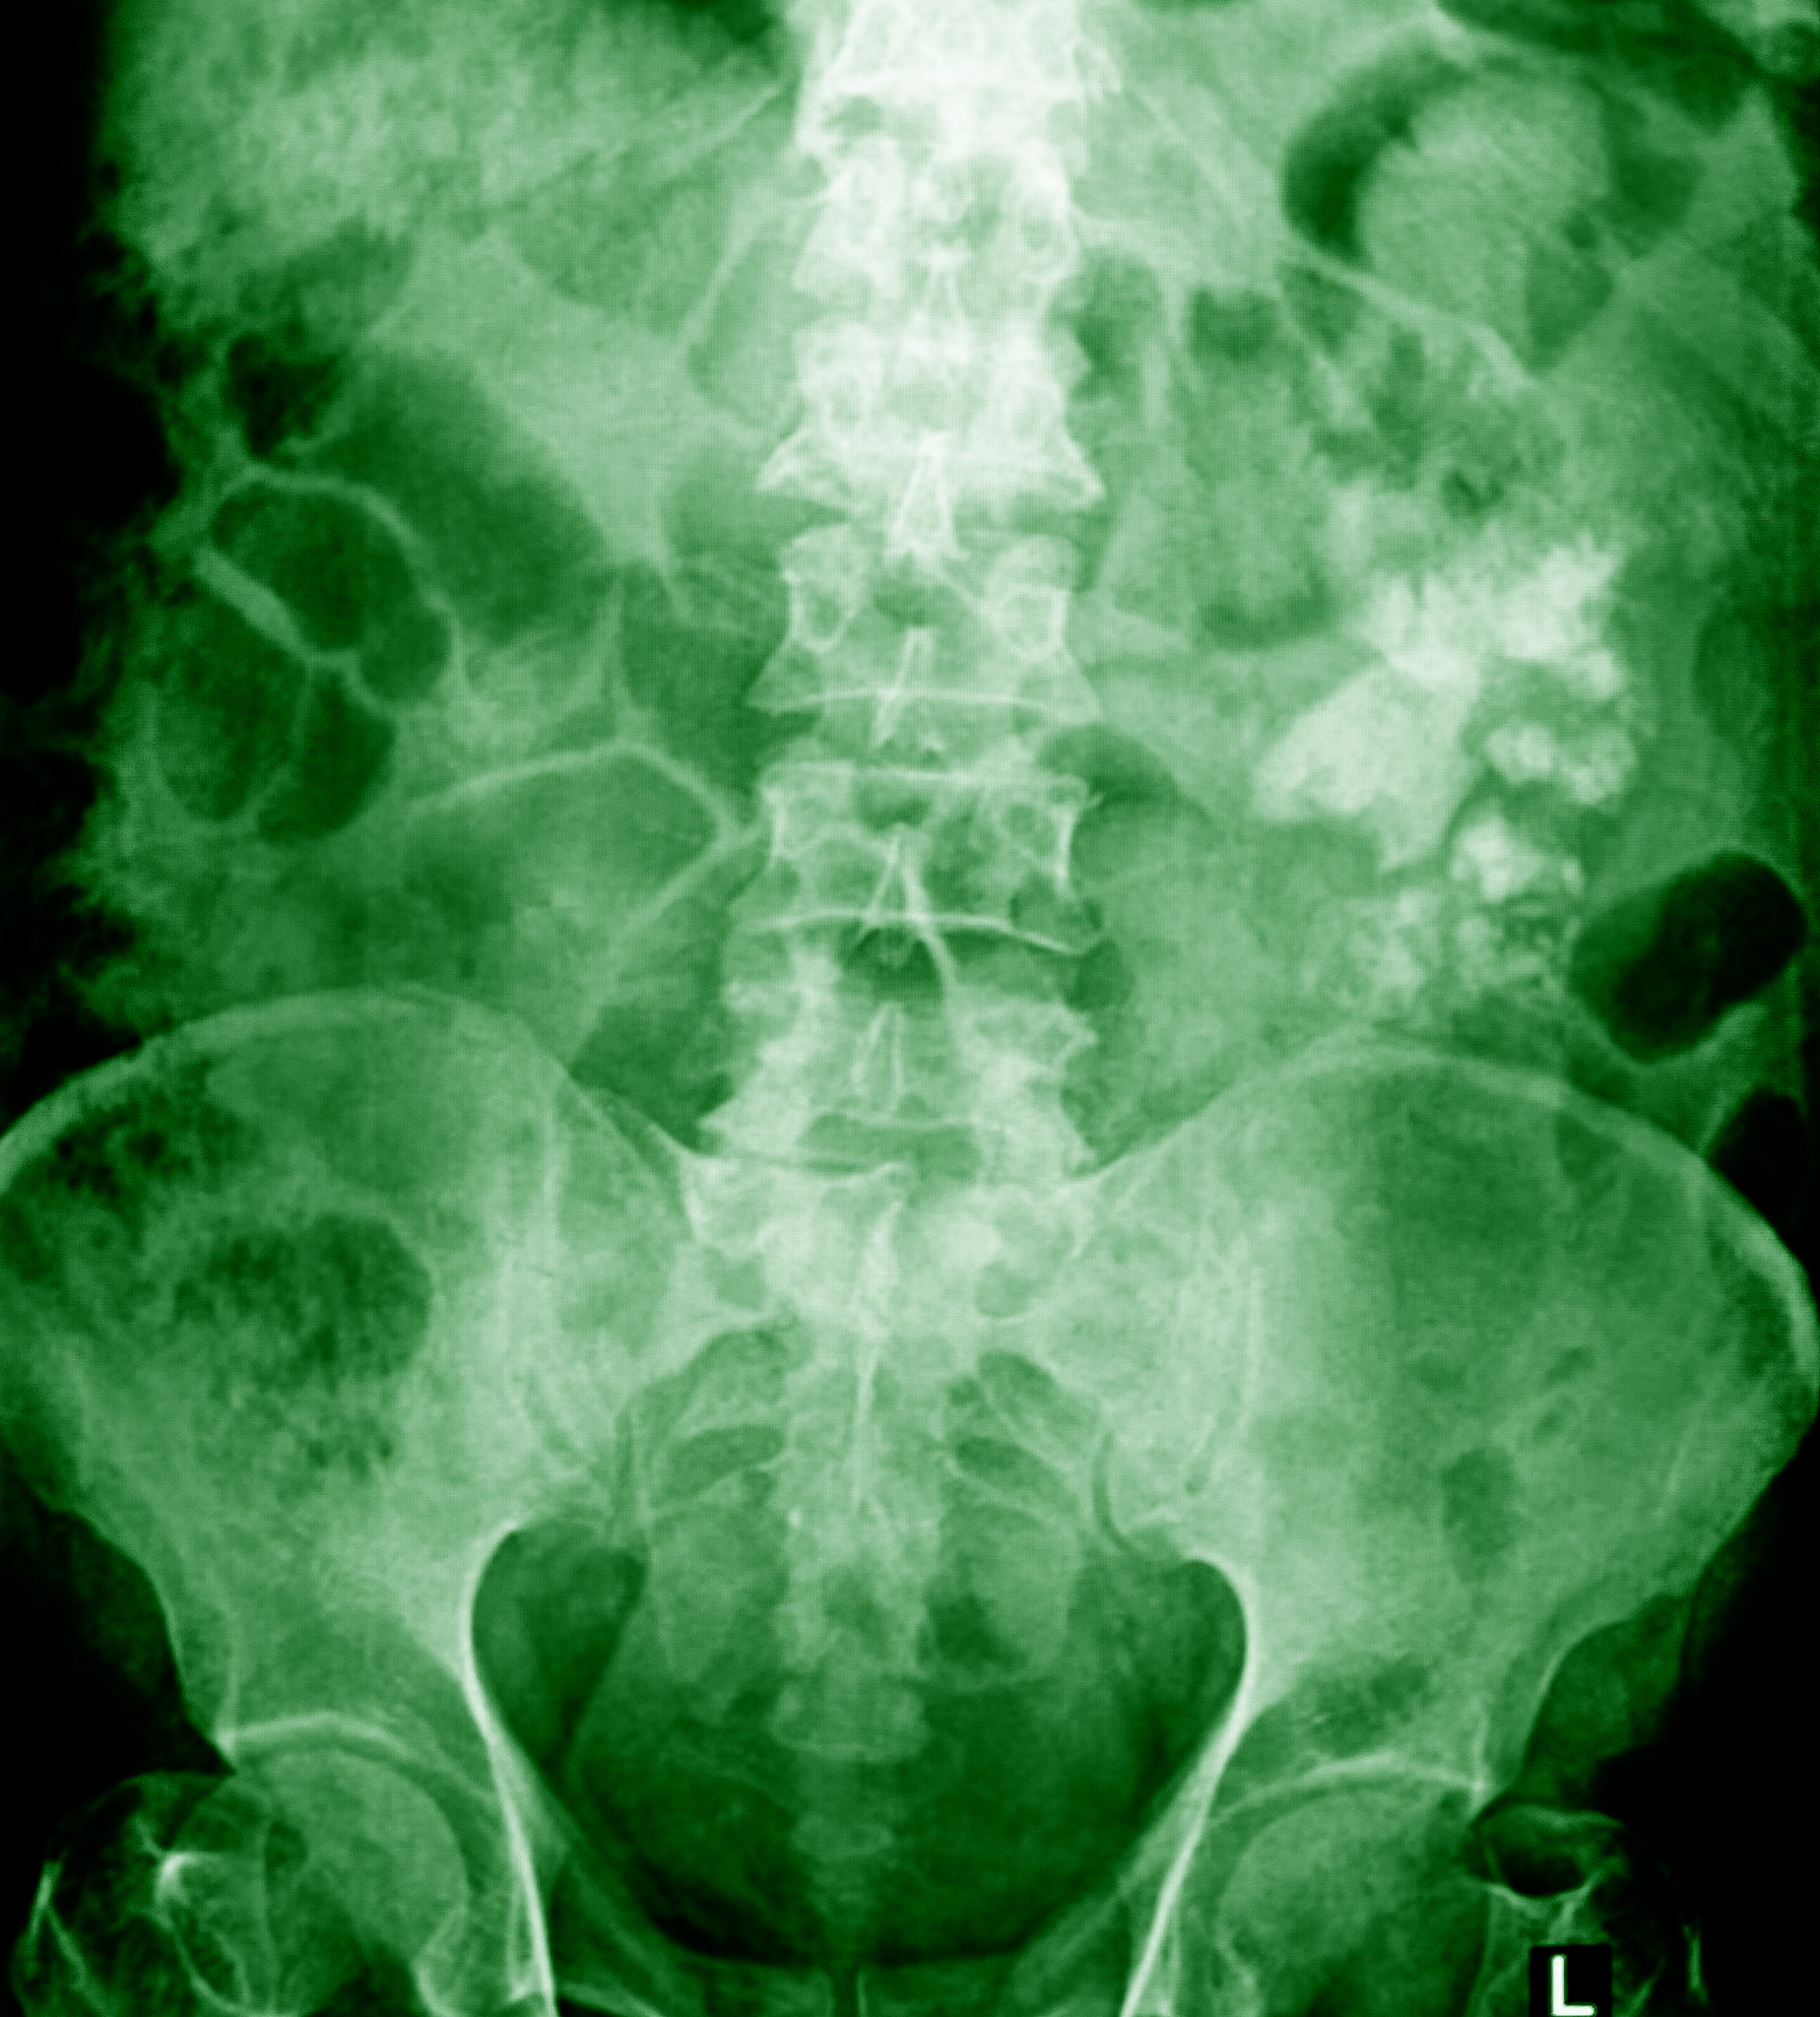

医生会根据病史、体格检查和相关检查结果进行诊断:

• 尿液分析: 检查尿液中是否存在红细胞、白细胞、结晶等。* 血液检查: 评估肾功能和炎症指标。* 影像学检查: * X线: 简单、经济,可初步判断结石大小、位置。 * 超声: 无辐射,可观察肾脏结构、结石大小和位置。 * CT: 最准确的检查方法,可清晰显示结石大小、位置、密度等信息。